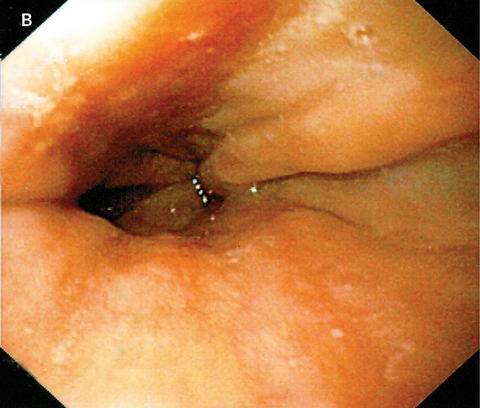

We describe a previously unreported association between hyoscine hydrobromide and severe oesophagitis, with ulceration visible almost to the submucosa in the distal oesophagus. The condition resolved with cessation of tablets and 2 months’ treatment with a proton-pump inhibitor.

Medication-induced oesophagitis may result from either local or systemic effects of a drug. Direct mucosal injury occurs after prolonged exposure of the oesophageal mucosa to the caustic contents of the medication.2 Examples of medications known to cause this type of injury include tetracycline, aspirin and non-steroidal anti-inflammatory drugs, as well as alendronate, potassium chloride, and iron compounds. Endoscopy often reveals a discrete ulcer with relatively normal surrounding mucosa.3 Risk factors for retention of pills in the oesophagus include a lack of adequate liquid bolus, lying down after swallowing, and older age.2,4

Although we could find no reports of hyoscine hydrobromide having a direct toxic effect on the oesophagus, the related compound hyoscine butylbromide has been shown to significantly increase the number of reflux episodes compared with placebo,5 in contrast with atropine, another anticholinergic, which has been shown to reduce reflux episodes.6 If hyoscine hydrobromide acts similarly to hyoscine butylbromide, it would be reasonable to hypothesise that the oesophagitis in our patient may be secondary to prolonged acid exposure. As the tablets were consumed without water, it is also possible that local mucosal injury may have occurred due to retention of tablets in the lower oesophagus, with subsequent pressure necrosis or caustic injury. Further studies would be required to elucidate the precise mechanism of injury.